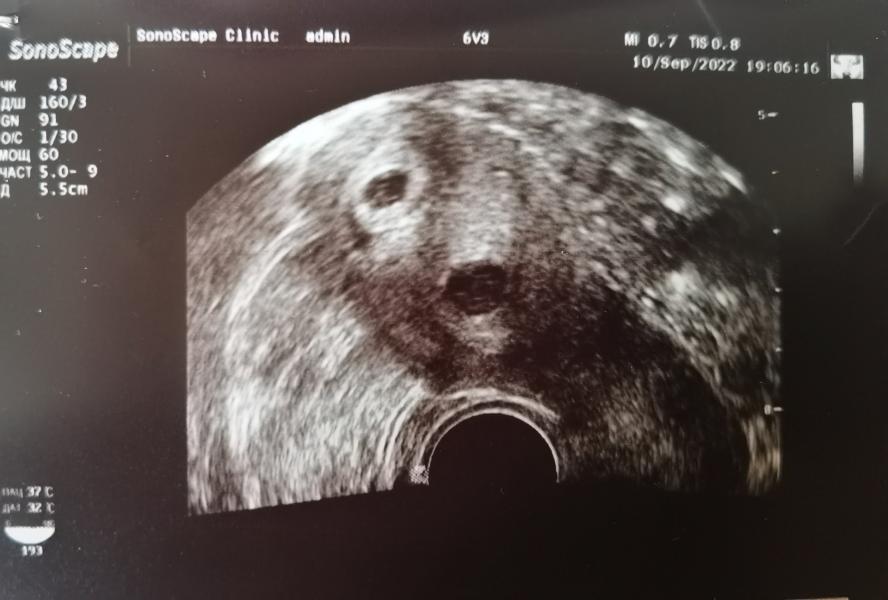

В выходные было первое узи, увидели плодное яйцо в матке (на снимке сверху). Внематочная – это один из моих самых больших страхов ещё с первой беременности.

Ещё откуда-то взялась миома (на снимке снизу), которой отродясь не было и которая больше плодного яйца.